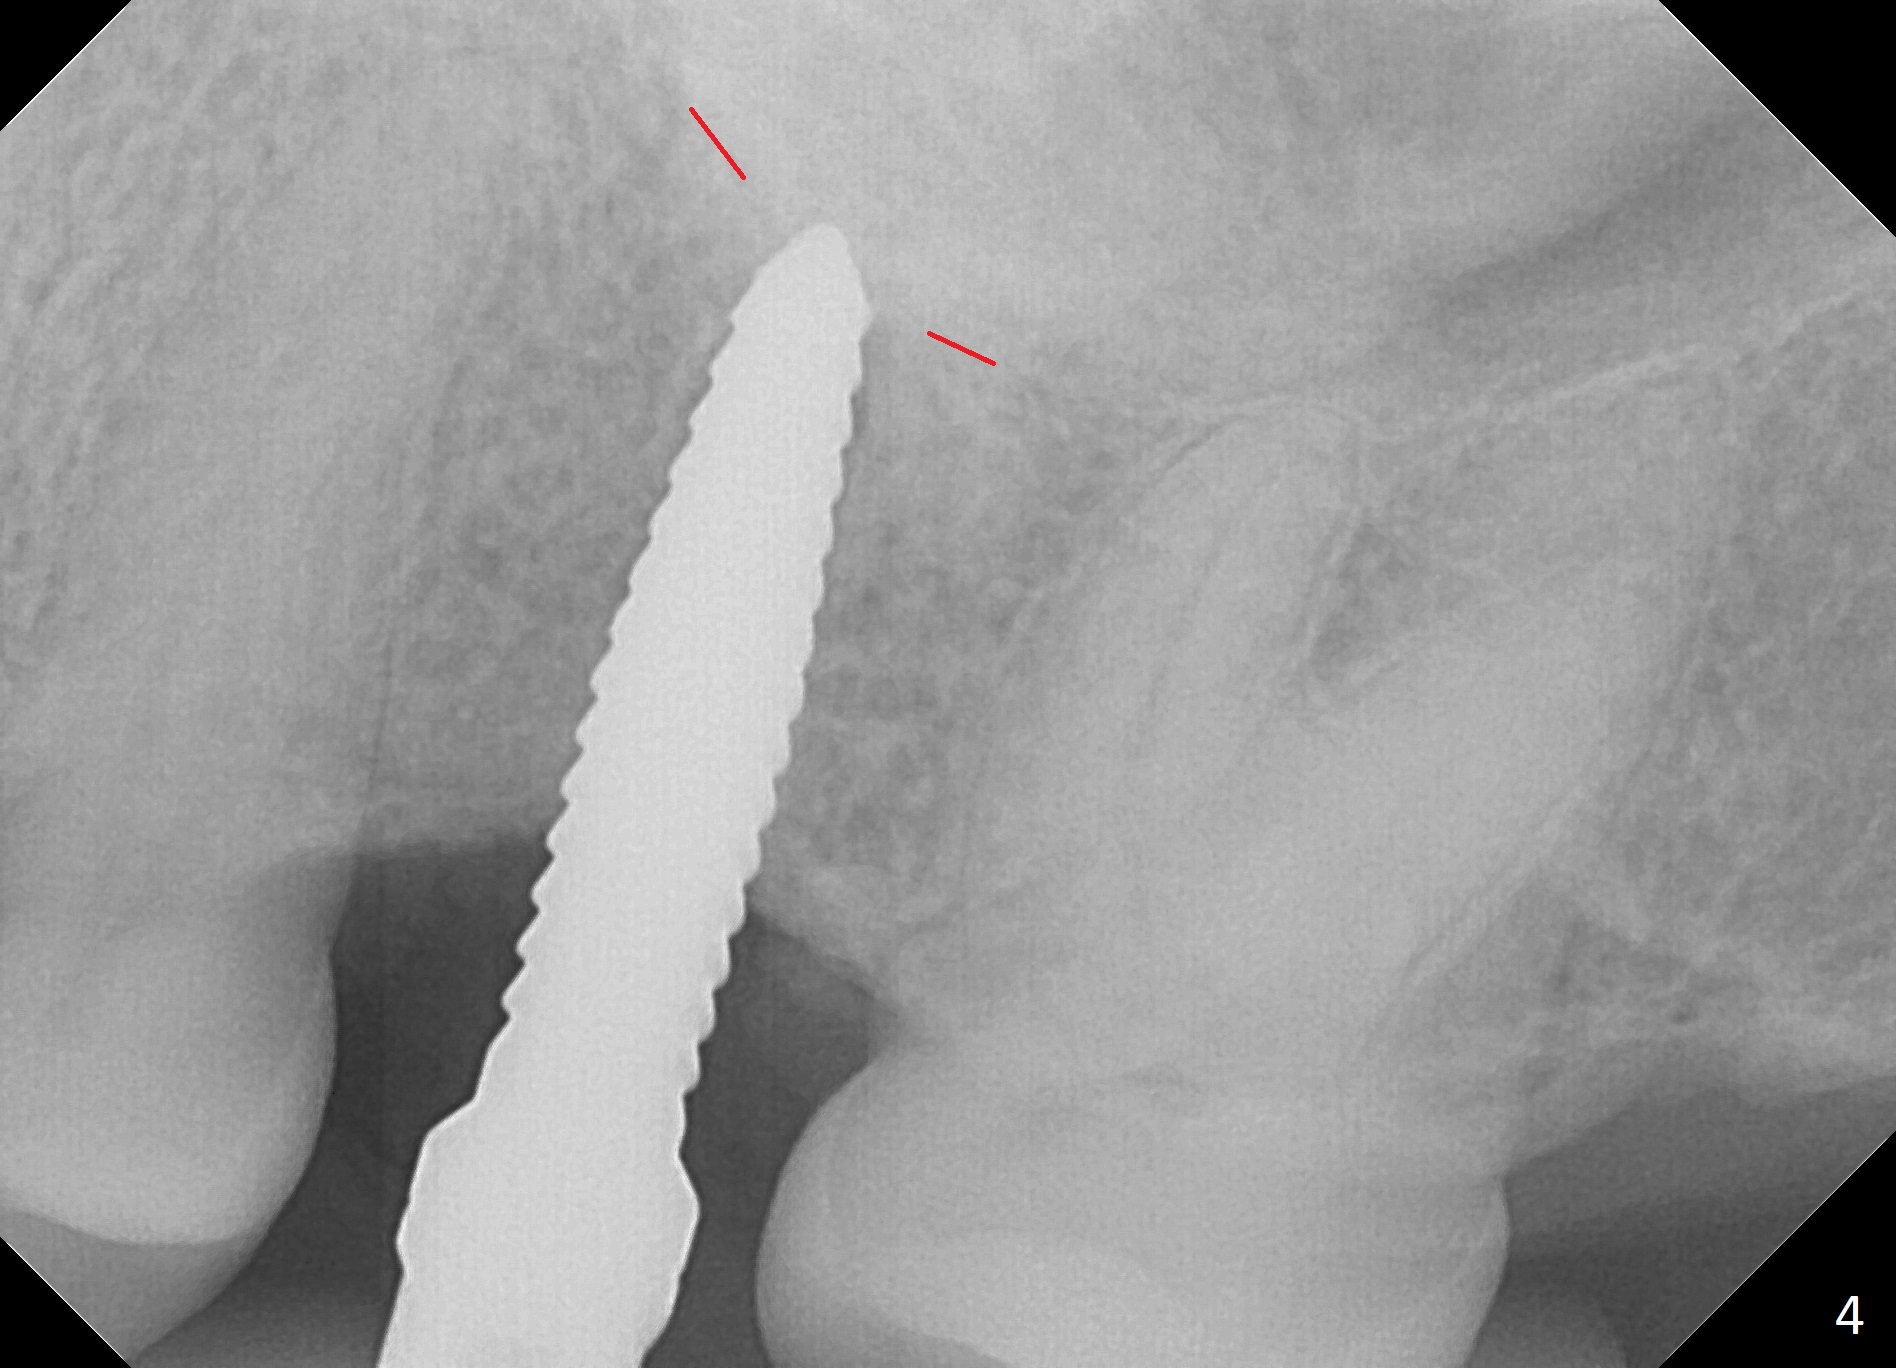

The edentulous area at #14 is moderately atrophic, After incision, the bone is too hard for #15 blade for bone expansion. Osteotomy is initiated with 1.2 mm drill, followed by insertion 1.3/2.3 mm bone expander (Fig.1). Use the same instruments are reused twice to change the trajectory (Fig.2,3). Finally Lindamann bur is utilized to move the osteotomy distally by ~ 2 mm; bone expansion continues until 2.4/3.7 mm expander for 13 mm with 50 Ncm (Fig.4). The last expander 3/4.4 mm barely enters the osteotomy for 6 mm. A 3.7 mm drill has to be used for 12 mm before placement of a 4.5x11.5 mm implant with >35 Ncm (Fig.5). A 5.5x5(3) mm abutment is placed with allograft (<) placed around the implant. Following suturing, periodontal dressing is applied around the implant. The abutment dislodges 3 months postop (Fig.6). Crown is delivered 3 weeks later. The abutment screw is retightened ~ 2 months later. He is a bruxer. The abutment screw is loose again <2 years post cementation (6 months post #18 screw retightenting and occlusal reduction), probably related to distal implant placement (Fig.7).